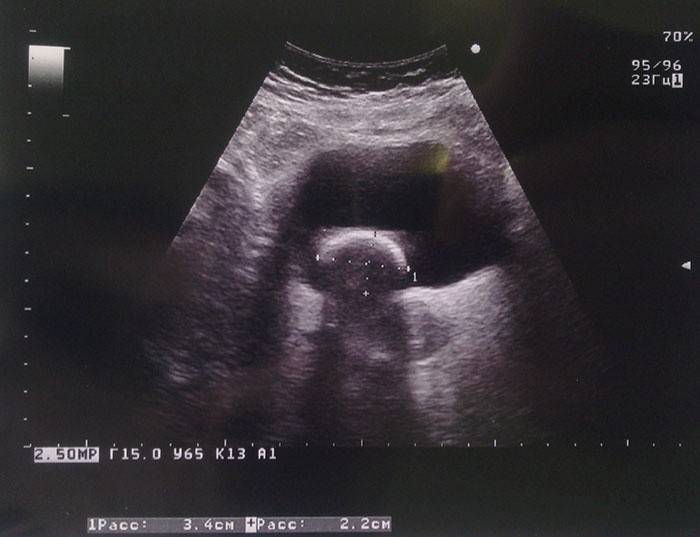

Decifrando um ultra-som da bexiga

Decifrar os resultados do ultrassom ajuda o médico a avaliar adequadamente a condição da bexiga e, em conjunto com as queixas do paciente, faz um diagnóstico preciso e prescreve o tratamento, se necessário. Afinal, nem sempre uma imagem de eco normal indica a ausência de problemas com a bolha. Nesse caso, é muito importante que o médico conheça indicadores aceitáveis para o exame correto. Um formato redondo ou oval de órgão, bordas lisas e volume variando de 350 a 750 ml nos homens e 250-550 ml nas mulheres são considerados normais.